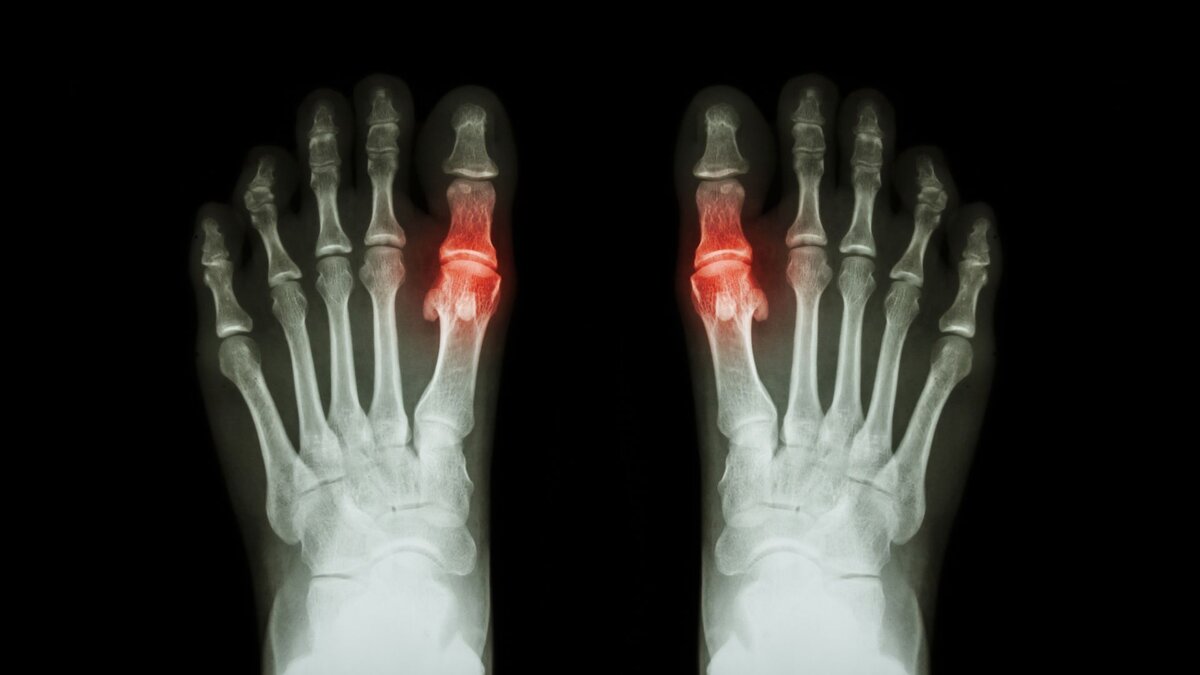

Подагра — это распространенный тип артрита, который может поражать любой сустав, чаще всего большой палец ноги. Обострения могут сопровождаться болью, отеком, покраснением и затруднением движений в суставе.

Подагра возникает из-за высокого уровня мочевой кислоты в организме. Она в свою очередь образуется, когда организм расщепляет пурины — химические вещества, естественным образом присутствующие в организме и в некоторых продуктах питания. Избыток мочевой кислоты приводит к образованию кристаллов в суставах, которые вызывают болезненные приступы.